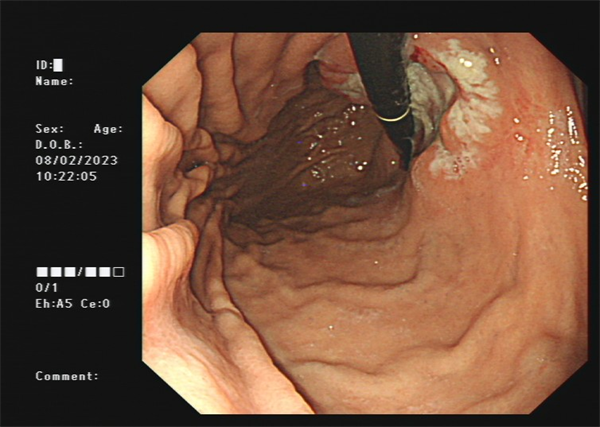

患者周某,男60岁,体检行肠镜发现直肠肿物,行肠镜下直肠黏膜下剥离术(ESD),术后病理:绒毛状管状腺瘤,局灶呈高级别上皮内瘤变。

· 食管、胃、结直肠早期癌粘膜下剥离术(ESD)